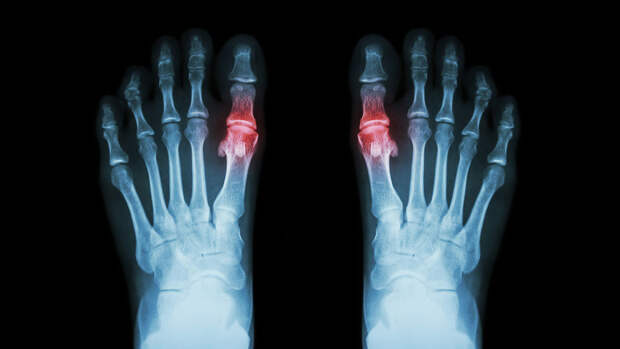

Подагра — это распространенная форма артрита, которая вызывается высоким уровнем мочевой кислоты, откладывающейся в суставах и вокруг них в виде игольчатых кристаллов. Их разрушение приводит к сильному воспалению в течение 1-2 недель, которое сопровождается сильным отеком, покраснением и болезненностью. От подагры страдает 1 из 40 взрослых людей в Великобритании.